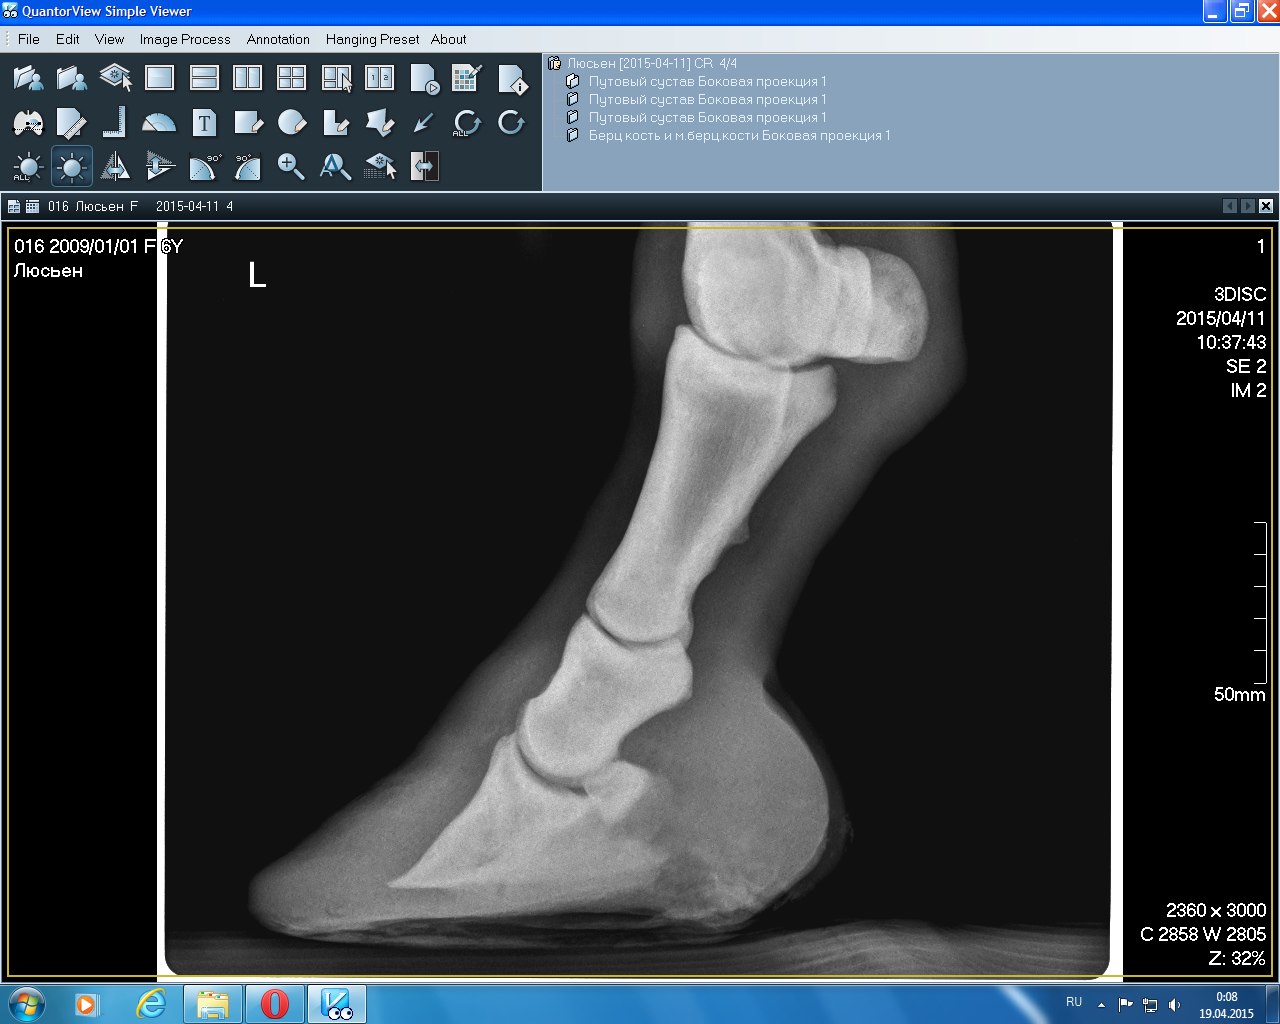

Левый перед(2015)